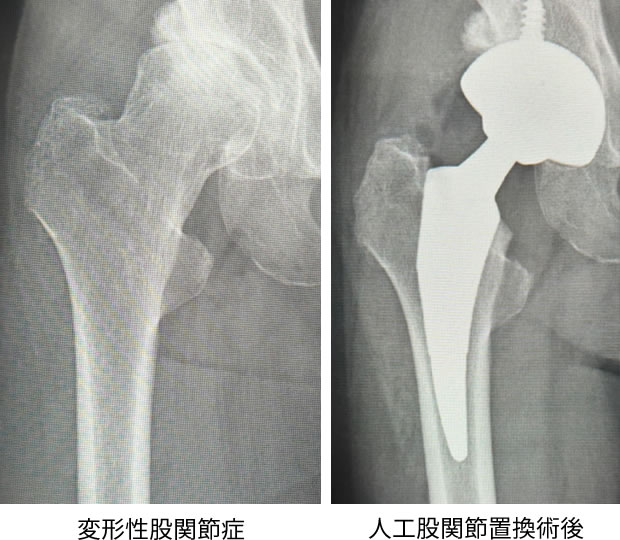

人工股関節置換術(Total hip arthroplasty:THA)は、変形性股関節症をはじめ関節リウマチ、大腿骨頭壊死、大腿骨頸部骨折など股関節を形成する寛骨臼(かんこつきゅう:骨盤側の関節面)や大腿骨頭(だいたいこっとう:大腿骨側の関節面)に問題のある患者さんの寛骨臼および大腿骨頭をインプラントと呼ばれる人工物に取り替えることで痛みを取り除き、日常生活を改善するために行われる手術です。